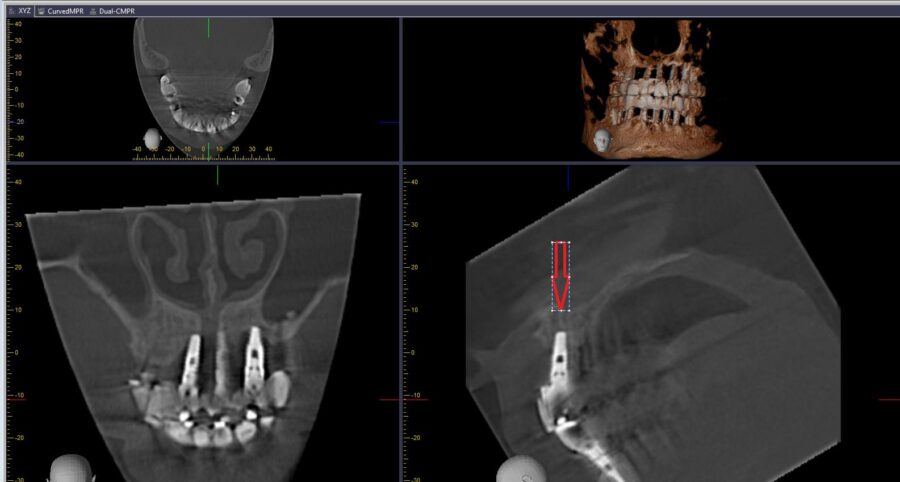

Các Biến Chứng Implant Nha Khoa: Phần 1 – Tổng Quan Thành Công Và Thất Bại

Tổng hợp đầy đủ về hệ thống Implant MegaGen (Hàn Quốc): dòng AnyRidge với ren dao cắt độc...